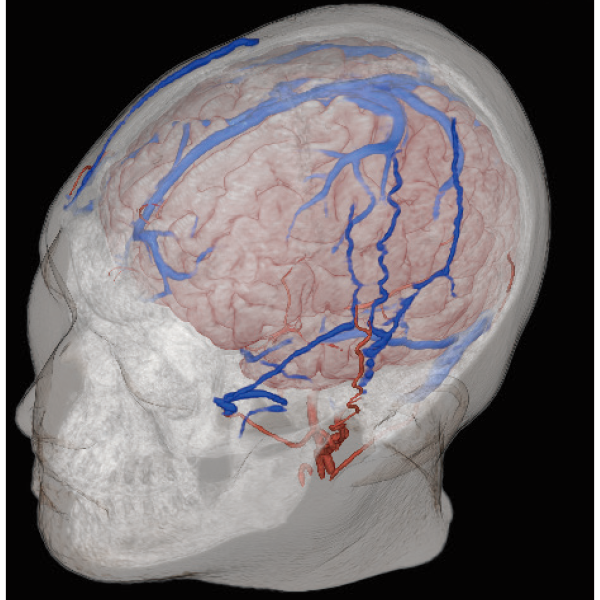

3DTOF MRA (MIP), 1:26